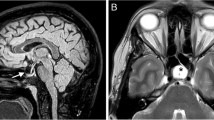

Hypertension is classified as primary or essential and secondary hypertension. When the cause of the hypertension is unknown, it is termed as primary hypertension which accounts for about 95% of cases of persistently raised BP. However, genetic factors in combination with environmental factors might play a role in the development of primary hypertension. For example, high sodium intake, physical inactivity, chronic high alcohol, tobacco intake, psychological stress, and low potassium and calcium intake are some of the environmental factors responsible for the development of primary hypertension [1]. Recent animal and cadaveric studies have shown that the brain stem hypoperfusion due to natural variations in vertebral arterial system anatomy could be responsible for a significant number of cases of idiopathic or essential hypertension [14,15,16]. Warnert et al. in their retrospective study using magnetic resonance imaging (MRI) showed a high incidence of vertebral artery hypoplasia (53%) and incomplete circle of Willis (64%) in hypertensive subjects as compared to 27% and 36% respectively in normotensive subjects, While treating hypertension, if the target BP cannot be attained with a diuretic-containing triple drug therapy at a maximum dose, it is termed as resistant hypertension. Before labeling as resistant hypertension, one should rule out the patient’s compliance with medication and all the secondary causes of hypertension. Recently studies have shown an association between posterior circulation hypoperfusion due to congenital variation in the circle of Willis and vertebral artery diameters and the development of essential hypertension [15, 16]. Sandell et al. have shown that pulsatile vertebral artery and the cranial nerve compression on the brain stem can cause hypertension which is often termed as neurogenic hypertension [17].

5 Pathophysiology of Neurogenic Hypertension

The rostral ventrolateral medulla (RVLM) located in the brain stem is the center of the neuronal regulation of BP and heart rate. The sympathoexcitatory C1 neurons are located beneath the surface of the brain stem in the RVLM, so stimulation of this area can cause sympathetic activation [17]. On the other hand, a depressor region in caudal medulla can reduce the sympathetic activity by direct inhibition of the RVLM and by stimulation of medullary parasympathetic centre. Various studies have shown that the neurovascular pulsatile compression (NVPC) of the RVLM by the posterior inferior cerebellar artery or the left vertebral artery was responsible for neurogenic hypertension, with gradual normalisation of BP after neurovascular decompression [18]. Furthermore, pulsatile compression of RVLM and C1 neuron can stimulate the SNS and activates angiotensin II (AngII) production causes vasoconstriction and endothelial dysfunction, which inturn causes overexpression of neural factor leading to vascular inflammation and remodeling. Additionally, an increased expression of ET-1 and NADPH oxidase-derived reactive oxygen species (ROS) results in neurogenic hypertension which is explained in detail in the section on cerebrovascular remodeling.